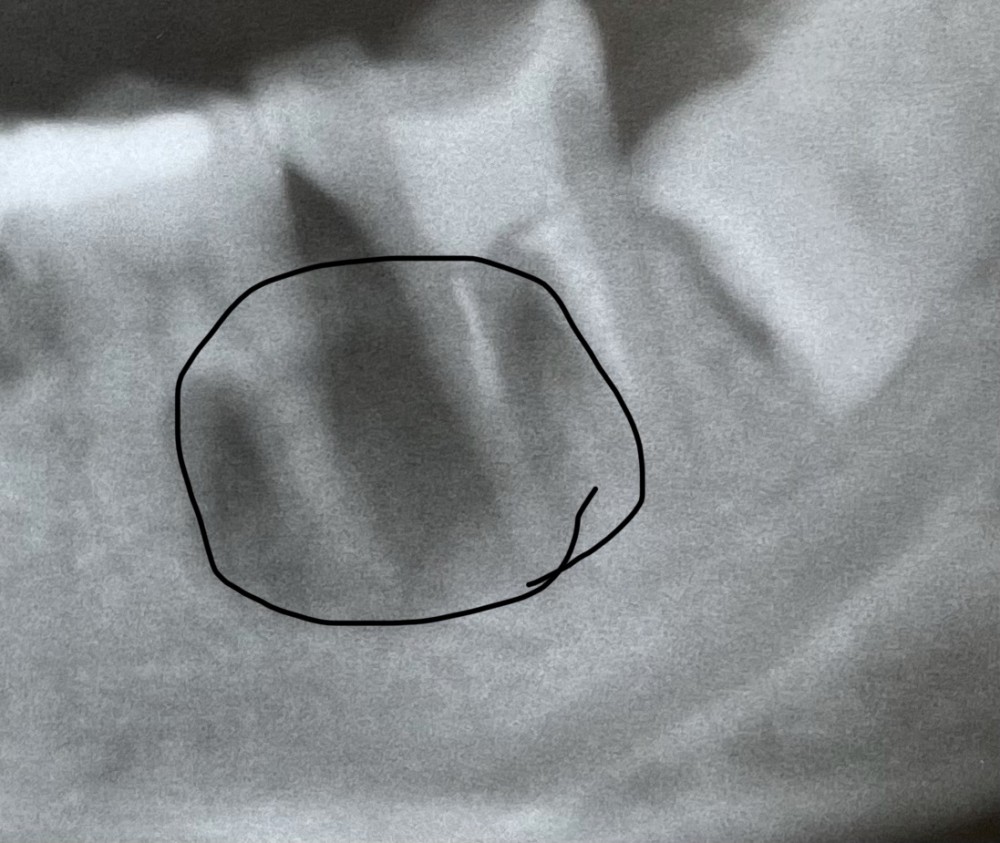

さっきと同じエックス線写真です。

今回は、必要な検査をしたのち、オレンジ色で囲んだ部分にバイ菌が入り込んで病巣ができたと診断し、治療に取り掛かりました。